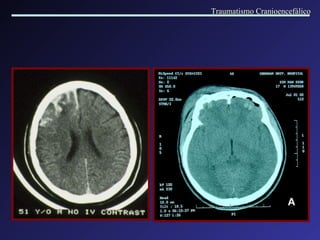

Lesão Axonal Difusa A lesão axonal difusa é mais frequentemente observada nas interfaces de tecidos com diferentes densidades. Os locais de acometimento mais comuns são: região cortico-subcortical nas regiões frontal e t emporal , corpo caloso,  fornix,  tronco cerebral, núcleos da base,  c á psul a interna. A RM é muito mais sensível na detecção destas lesões. Traumatismo Cranioencefálico

Lesão Axonal Difusa Traumatismo Cranioencefálico

Traumatismo Cranioencefálico